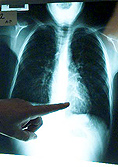

pulmonesOtro cáncer que sigue en aumento en Chile, según explica Rubén Urrejola, es el de pulmón. "Es más complicado de diagnosticar, porque tampoco da síntomas inicialmente, que es la etapa en que quisiéramos diagnosticarlo y las radiografías de tórax, desgraciadamente, no muestran lesiones muy pequeñas, sino cuando han adquirido cierto volumen". Agrega que no existe en este minuto un examen cuyo costo-efectividad se haya comprobado para hacer un diagnóstico precoz de cáncer de pulmón. Eso sí, en pacientes mayores de 40 y con antecedentes, debiera aconsejarse un scanner del tórax en algún momento, con el que se podría diagnosticar una lesión muy inicial.